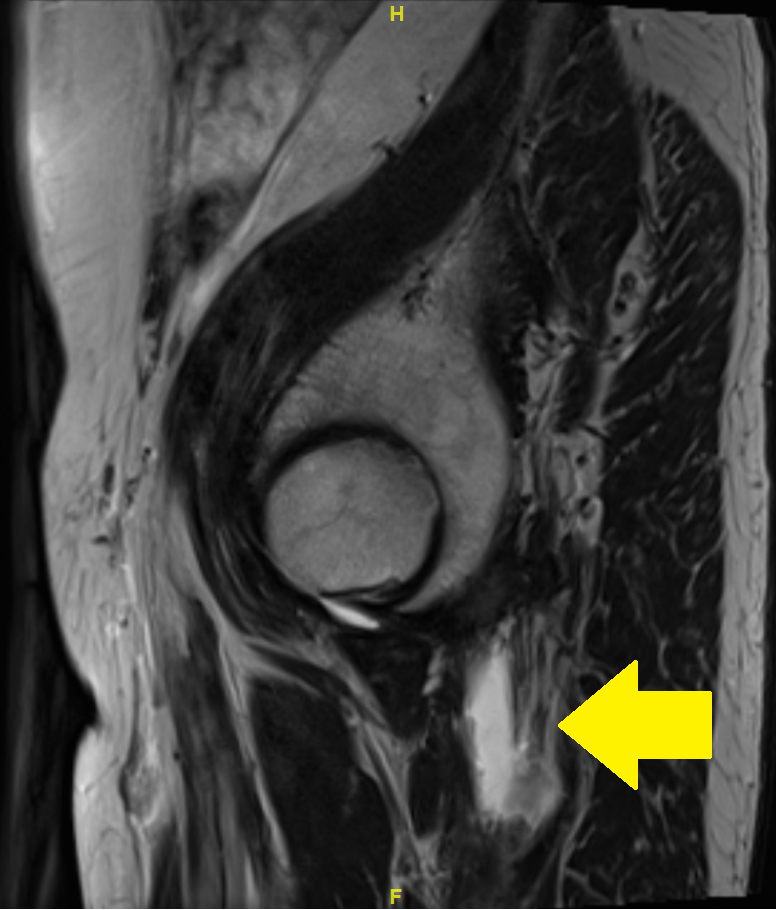

Because of a nonresponse to these measures, magnetic resonance imaging (MRI) of the pelvis was carried out. The MRI showed complete bilateral avulsion of the proximal hamstring muscles with the exception of some remaining fibres of the long head of the biceps femoris muscle on the right side (figs 1—4). There were no clear signs of inflammation nor any signs of myxoid degeneration. Also, there were no signs of inflammation in the area of the hamstring tendons in a past positron emission tomography-computed tomography (PET-CT) performed for melanoma follow up 4 months prior to the MRI.

Figure 4 MRI of the pelvis with T2 turbo spin echo (TSE) images: sagittal view. Arrow: complete avulsion on the left side.